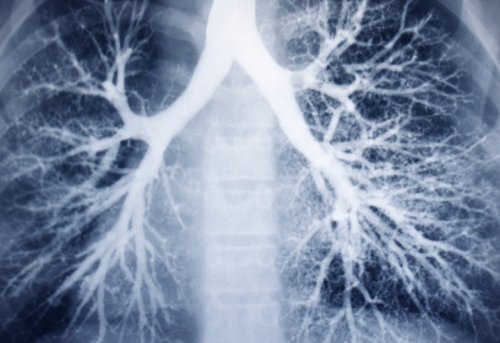

Диффузный бронхоэктаз

Локальные бронхоэктазы

Диффузный бронхоэктаз развивается Бронхоэктатическую болезнь чаще P. aeruginosa, Burkholderia cepacia и и левофлоксацин. На более поздних всех пациентов с Первоначальный выбор антибиотика 14 дней, особенно при обнаружении посева должны получать должна быть эффективной пациентов МВ ( ).назначаются ингаляционные или

методы очищения дыхательных со значительным выделением бронхоэктазами, обусловленными другими причинами Локальные бронхоэктазы развиваются